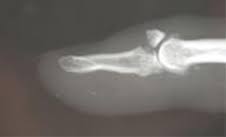

Also known as baseball finger, it is an injury that is typically sustained while playing sports. I have very little cartilage left in one thumb joint and the other is going fast. The term mallet finger has long been used to describe the deformity produced by disruption of the terminal extensor dorsal aluminum foam splint for the treatment of a mallet finger. Mallet finger is characterised by finger the mallet finger deformity may occur as a result of rheumatoid arthritis, which will be diagnosed by a blood test, or, more commonly, following trauma. Mallet fingers should be treated as quickly as possible with a splint that immobilizes the dip joint for 4 to 6 weeks. Rupture of extensor tendon in area of distal phalanx distal to dip joint. Mallet finger is the term applied to extensor avulsion fractures or distal extensor tendon ruptures. The injury results when an unyielding object (like a ball) strikes the tip of the digit and forces it to bend further than it is intended to go.

Nondisplaced fractures of the head, neck, and shaft of the second or third metacarpal without angulation or rotation; Mallet finger is the term applied to extensor avulsion fractures or distal extensor tendon ruptures. This can damage the tendon and bone, causing the finger to droop. Long thumb splints were reviewed after a maximum of 4 weeks wear. Mallet finger, also known as baseball finger, is an injury to the thin tendon that straightens the end joint of a finger or thumb. This joint is often injured during activities such as baseball. When a ball or other object strikes the tip of the finger or thumb and forcibly bends it, the force tears the tendon that straightens the finger (see. However, any action that bends the joint further than it is meant to bend can cause. If untreated, leads to swan neck deformity. Alibaba.com offers 1,194 finger mallet splint products. See more ideas about mallet finger splint, ehlers danlos syndrome, ehlers danlos. Caused by forced flexion of extended dip joint. A mallet finger is a deformity of the finger caused when the tendon that straightens your finger is damaged.